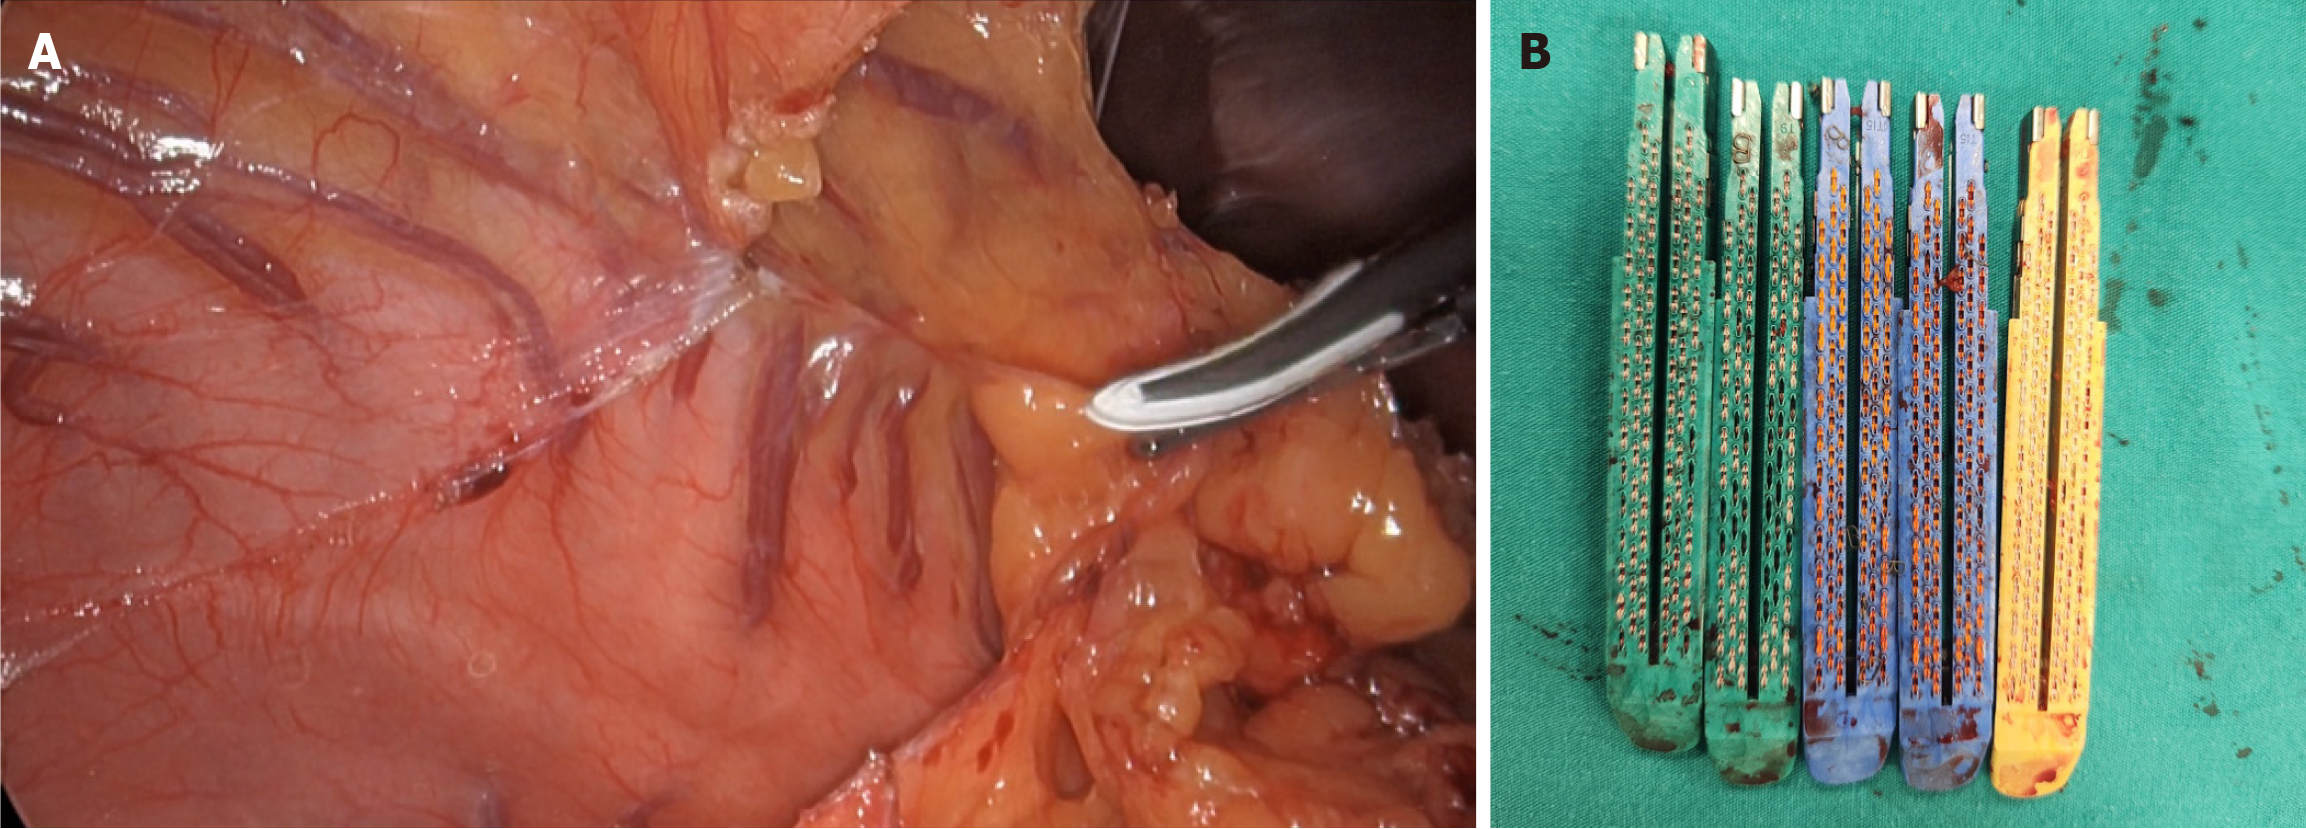

Figure 3 Laparoscopic view and total number and sizes of cartridges used during sleeve gastrectomy.

A: Dissection of the lesser omentum by division of the gastrocolic ligament; B: The number and size of endoscopic cartridges used during laparoscopic sleeve gastrectomy.